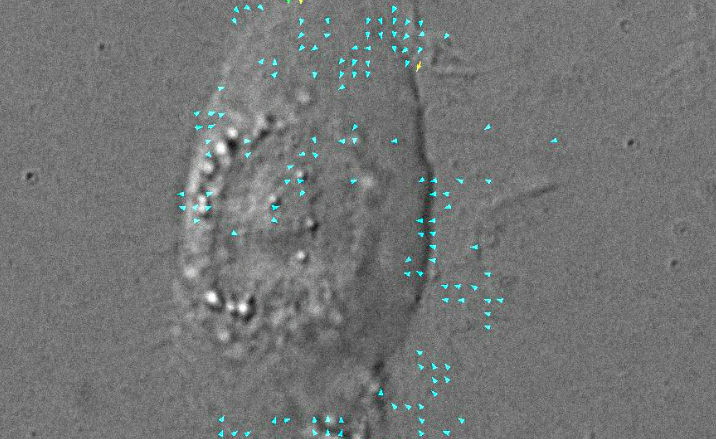

Il team è riuscito a scoprirlo iniettando nelle cellule delle sostanze fluorescenti, che le ha rese visibili al microscopio mentre camminavano. Negli studi sulla rigenerazione cellulare si utilizza spesso il Danio Rerio, conosciuto comunemente come pesce zebra. Questo pesce, infatti, possiede una notevole capacità di rigenerazione dei tessuti, tra cui la capacità di guarire arti danneggiati, cuore e anche il midollo spinale.

Il pesce zebra è stato poi sottoposto a diverse ferite sulla carne. L’obiettivo era quello di vedere come le cellule della pelle rispondevano a queste ferite, e per la gioia dei ricercatori, si è potuto osservare in tempo reale il processo di rigenerazione con una precisione senza precedenti.

Così, dopo l’amputazione di una pinna, gli studiosi hanno visto come le cellule della pelle sono migrate da zone vicine per coprire rapidamente l’incisione; poi, si sono prodotte nuove cellule per sostituire quelle vecchie danneggiate; infine, le cellule della pelle hanno aumentato la loro dimensione al fine di coprire tutta la ferita, permettendogli di guarire correttamente.